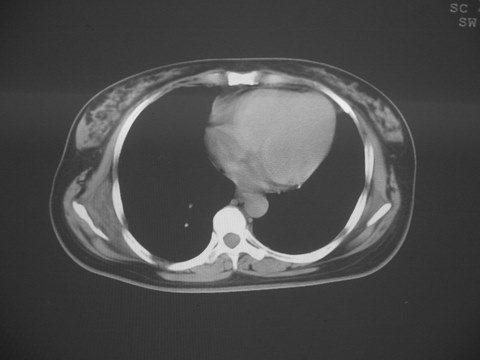

无意中发现右背部肩胛下缘半球状突起,无红,热,痛感觉。拍平片未见异常。ct发现右肩胛下角深层新月型软组织肿胀,ct值-50至15,大家看看是什么性质,来源,初步考虑来源于下后锯肿,考虑下后锯肌肿胀,可是病人无明确外伤史,也不疼痛

三、弹性纤维瘤影像

典型位于背部,在肩胛下角和胸壁软组织之间,肿瘤表面为菱形肌和背阔肌所被覆深部,紧邻肋骨和肋间肌,呈半圆形或扁豆状,宽基底与胸壁相交,边界比较清楚,相邻的肌肉和肋骨无侵蚀,部分病变与其表面的临近肌肉之间可受压呈弧形的脂肪界面,肿瘤周围软组织无水肿。

从mr表现可以推断ct影像,即肿块呈软组织密度,病灶内可出现脂肪密度的低密度影。